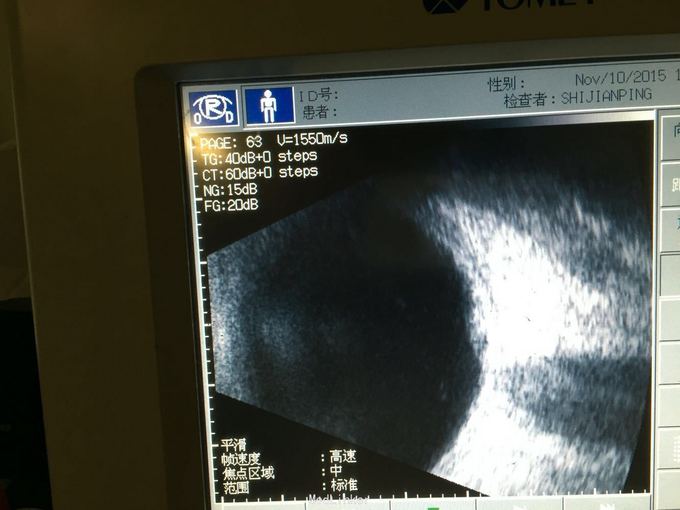

眼底出血一例

眼底出血

中年男性,右眼突发视物不见5天,无其他病史。

右眼眼底出血原因待排 动脉瘤? 脉黑?